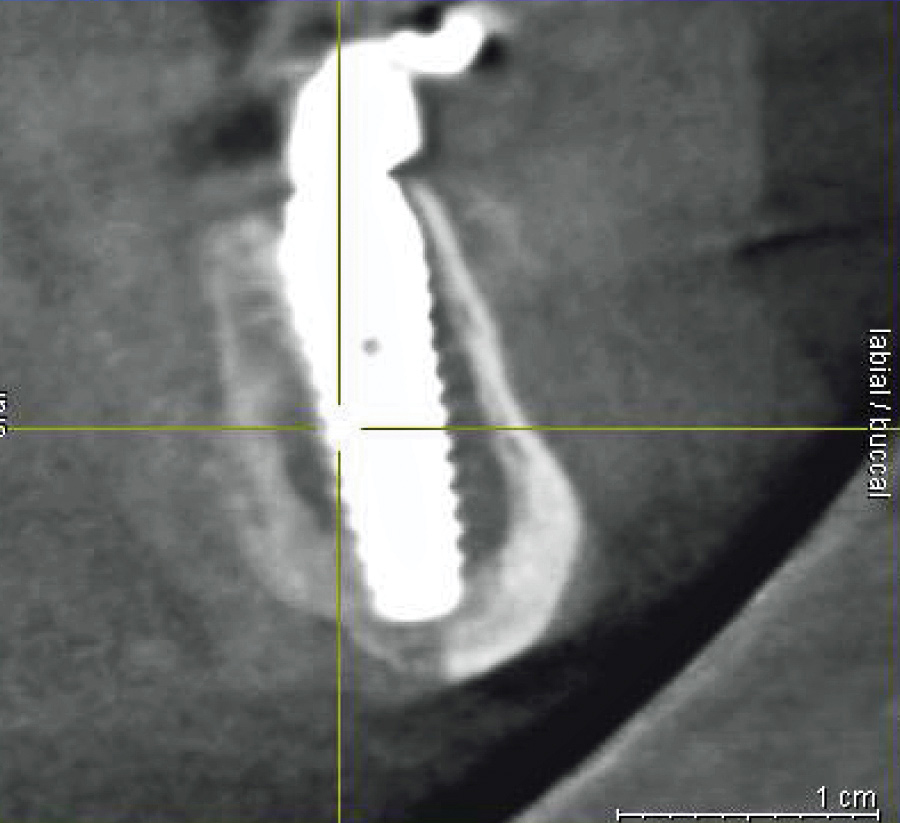

Fig 3. Presurgical cross-sectional CBCT scan slice of an All-on-4–style dental implant patient with crestal location of the inferior alveolar nerve (yellow crosshairs on nerve) secondary to bone resorption. Bone reduction in this location risks exposure and damage to the nerve.

Figure 3

In cases of severe mandibular atrophy, supracrestal exposure of the mental foramen or inferior alveolar nerve (Figure 3) may be possible.8,22 When encountered, these situations require special consideration for incision design, mucogingival flap reflection, bone reduction, dental implant placement, soft-tissue reduction, and suturing. With exposed nerve tissue, each of these steps has the potential for causing damage.

When faced with an exposed inferior alveolar nerve, the author has placed dehydrated human amnion-chorion membrane (DHACM) directly onto the nerve fibers based on the positive outcomes that have been reported with DHACM nerve wraps around the prostatic neurovascular bundle in prostatectomy surgeries.23 In 4 cases of DHACM that the author used inferior alveolar nerve wraps, patients reported no adverse outcomes, such as permanent or transient anesthesia, paresthesia, hypoesthesia, or dysesthesia.